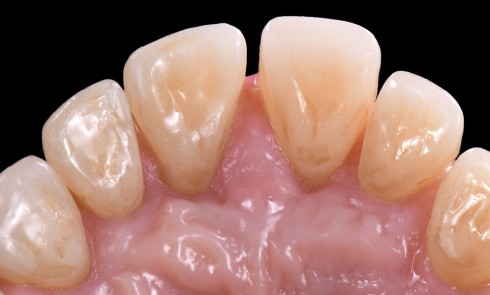

Article réservé à nos abonnés Technique de stratification composite guidée dans les secteurs postérieurs dans le cadre d’une réhabilitation globale avec augmentation de DVO

Dans le cadre d’une réhabilitation globale, l’analyse esthétique et fonctionnelle est désormais incontournable. Dans les situations d’usure modérées à sévères,...